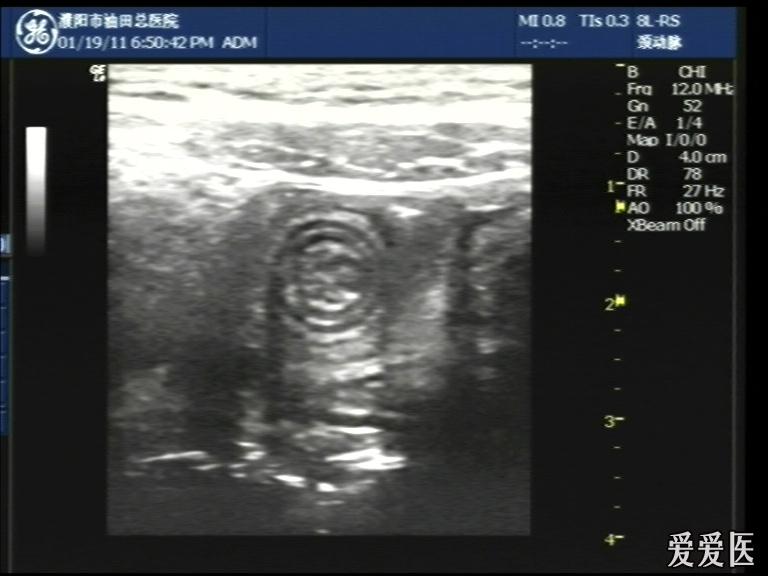

超声检查:于下腹部可见“双环征象”,双环重叠长约6mm,检查期间观察可见肠蠕动;CDFI:未见明显异常血流信号。

超声提示:下腹部双环征,考虑肠套叠可能,请结合临床

“套筒征”、“同心圆征”,很清晰,很经典!

好图,同心圆征。清晰